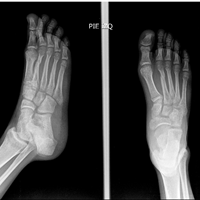

Fractura metatarsos

Pues bien, ahora mismo tienes el callo oseo, pero éste debe de ir reorganizandóse. Ahora mismo tienes hueso nuevo formado pero aún es frágil, y es normal que en empezar a apoyar peso en él (sobretodo de puntillas, que en ésta posición el peso del...

Después de 6 semanas de reposo por fractura en 5to metatarso ¿Es necesario una cirugía?

Ante todo decirle que la decisión es en función de la radiografía y de su estado, no de lo que yo pueda comentarle. El tiempo tiene que consolidar la fractura, pero si pasado el recomendable no hay una consolidación satisfactoria, es normal que el...